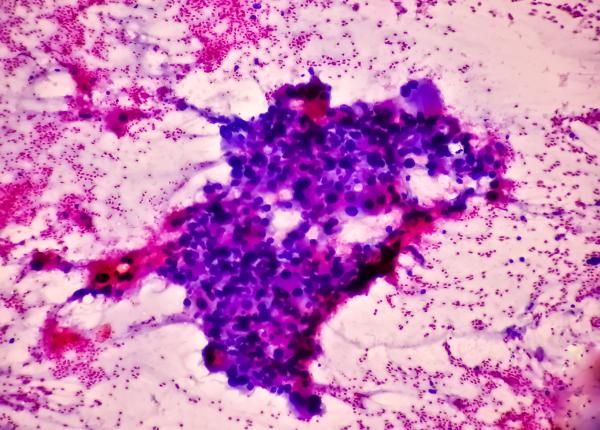

EXCLUSIV Imunoterapia și terapia personalizată pentru cancer: ce sunt. Fejer: E foarte bine acceptată de pacienți. O testare accesibilă, dar nu este finanțată de Casa de Asigurări

Imunoterapia are rolul de a stimula sistemul imun în contracararea celulelor canceroase. Ce este terapia personalizată în cancer.

EXCLUSIV Terapiile inovative, efect major. Coliță: Corectitudine a răspunsului terapeutic

Terapiile inovative își fac loc și în marile centre universitare din țară. Ce beneficii aduc pentru pacienți.